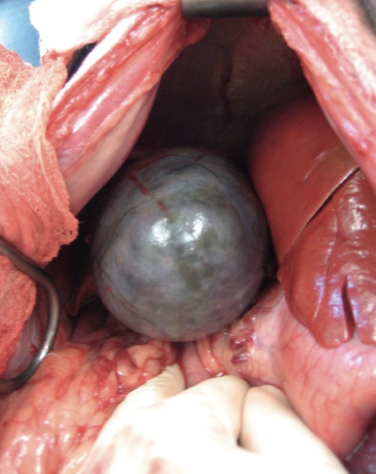

What is a gall bladder mucocele?

- Cystic mucosal hyperplasia resulting in hypersecretion of mucus and thick, gelatinous bile within the gall bladder which is generally sterile

- This can lead to obstruction and rupture

How are gall bladder mucoceles diagnosed?

- Clinicopathologic abnormalities: Elevated bili, ALP, ALT, and AST

- US: Non-dependent echogenic material in a stellate pattern (looks like a kiwi)

How are gall bladder mucoceles managed?

- Medical management for early cases

- Surgical management with cholecystectomy (ensure CBD patency)